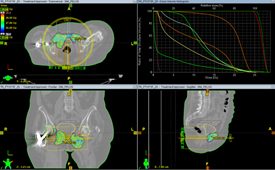

Пациентка N обратилась в клинику с жалобами на сильные боли в области седалищных костей, частично купирующиеся на фоне приема Трамадола. В связи с невозможностью опоры на левую нижнюю конечность (перелом шейки бедренной кости; в анамнезе остеосинтез по поводу перелома шейки правой бедренной кости) вынуждена большую часть времени находиться в сидячем положении, что в свою очередь усиливает болевой синдром.

При контрольных обследованиях выявлено метастатическое поражение лонных и седалищных костей с обеих сторон, больших размеров, с образованием обширных дефектов в костной ткани, с вовлечением мягких тканей и реактивным воспалением.

В связи с анатомической особенностью локализации метастатического процесса и размеров очагов с целью купирования болевого синдрома пациентке рекомендовано проведение паллиативного курса дистанционной лучевой терапии на область метастатических очагов в лонных и седалищных костях с обеих сторон в разовой дозе 5 Гр за 5 фракций (до суммарной дозы 25 Гр).

После 3-го сеанса пациентка отметила уменьшение болевого синдрома, нормализацию сна.

После окончания курса лучевой терапии в динамике отметила уменьшение болевого синдрома, отсутствие в необходимости приема Трамадола.